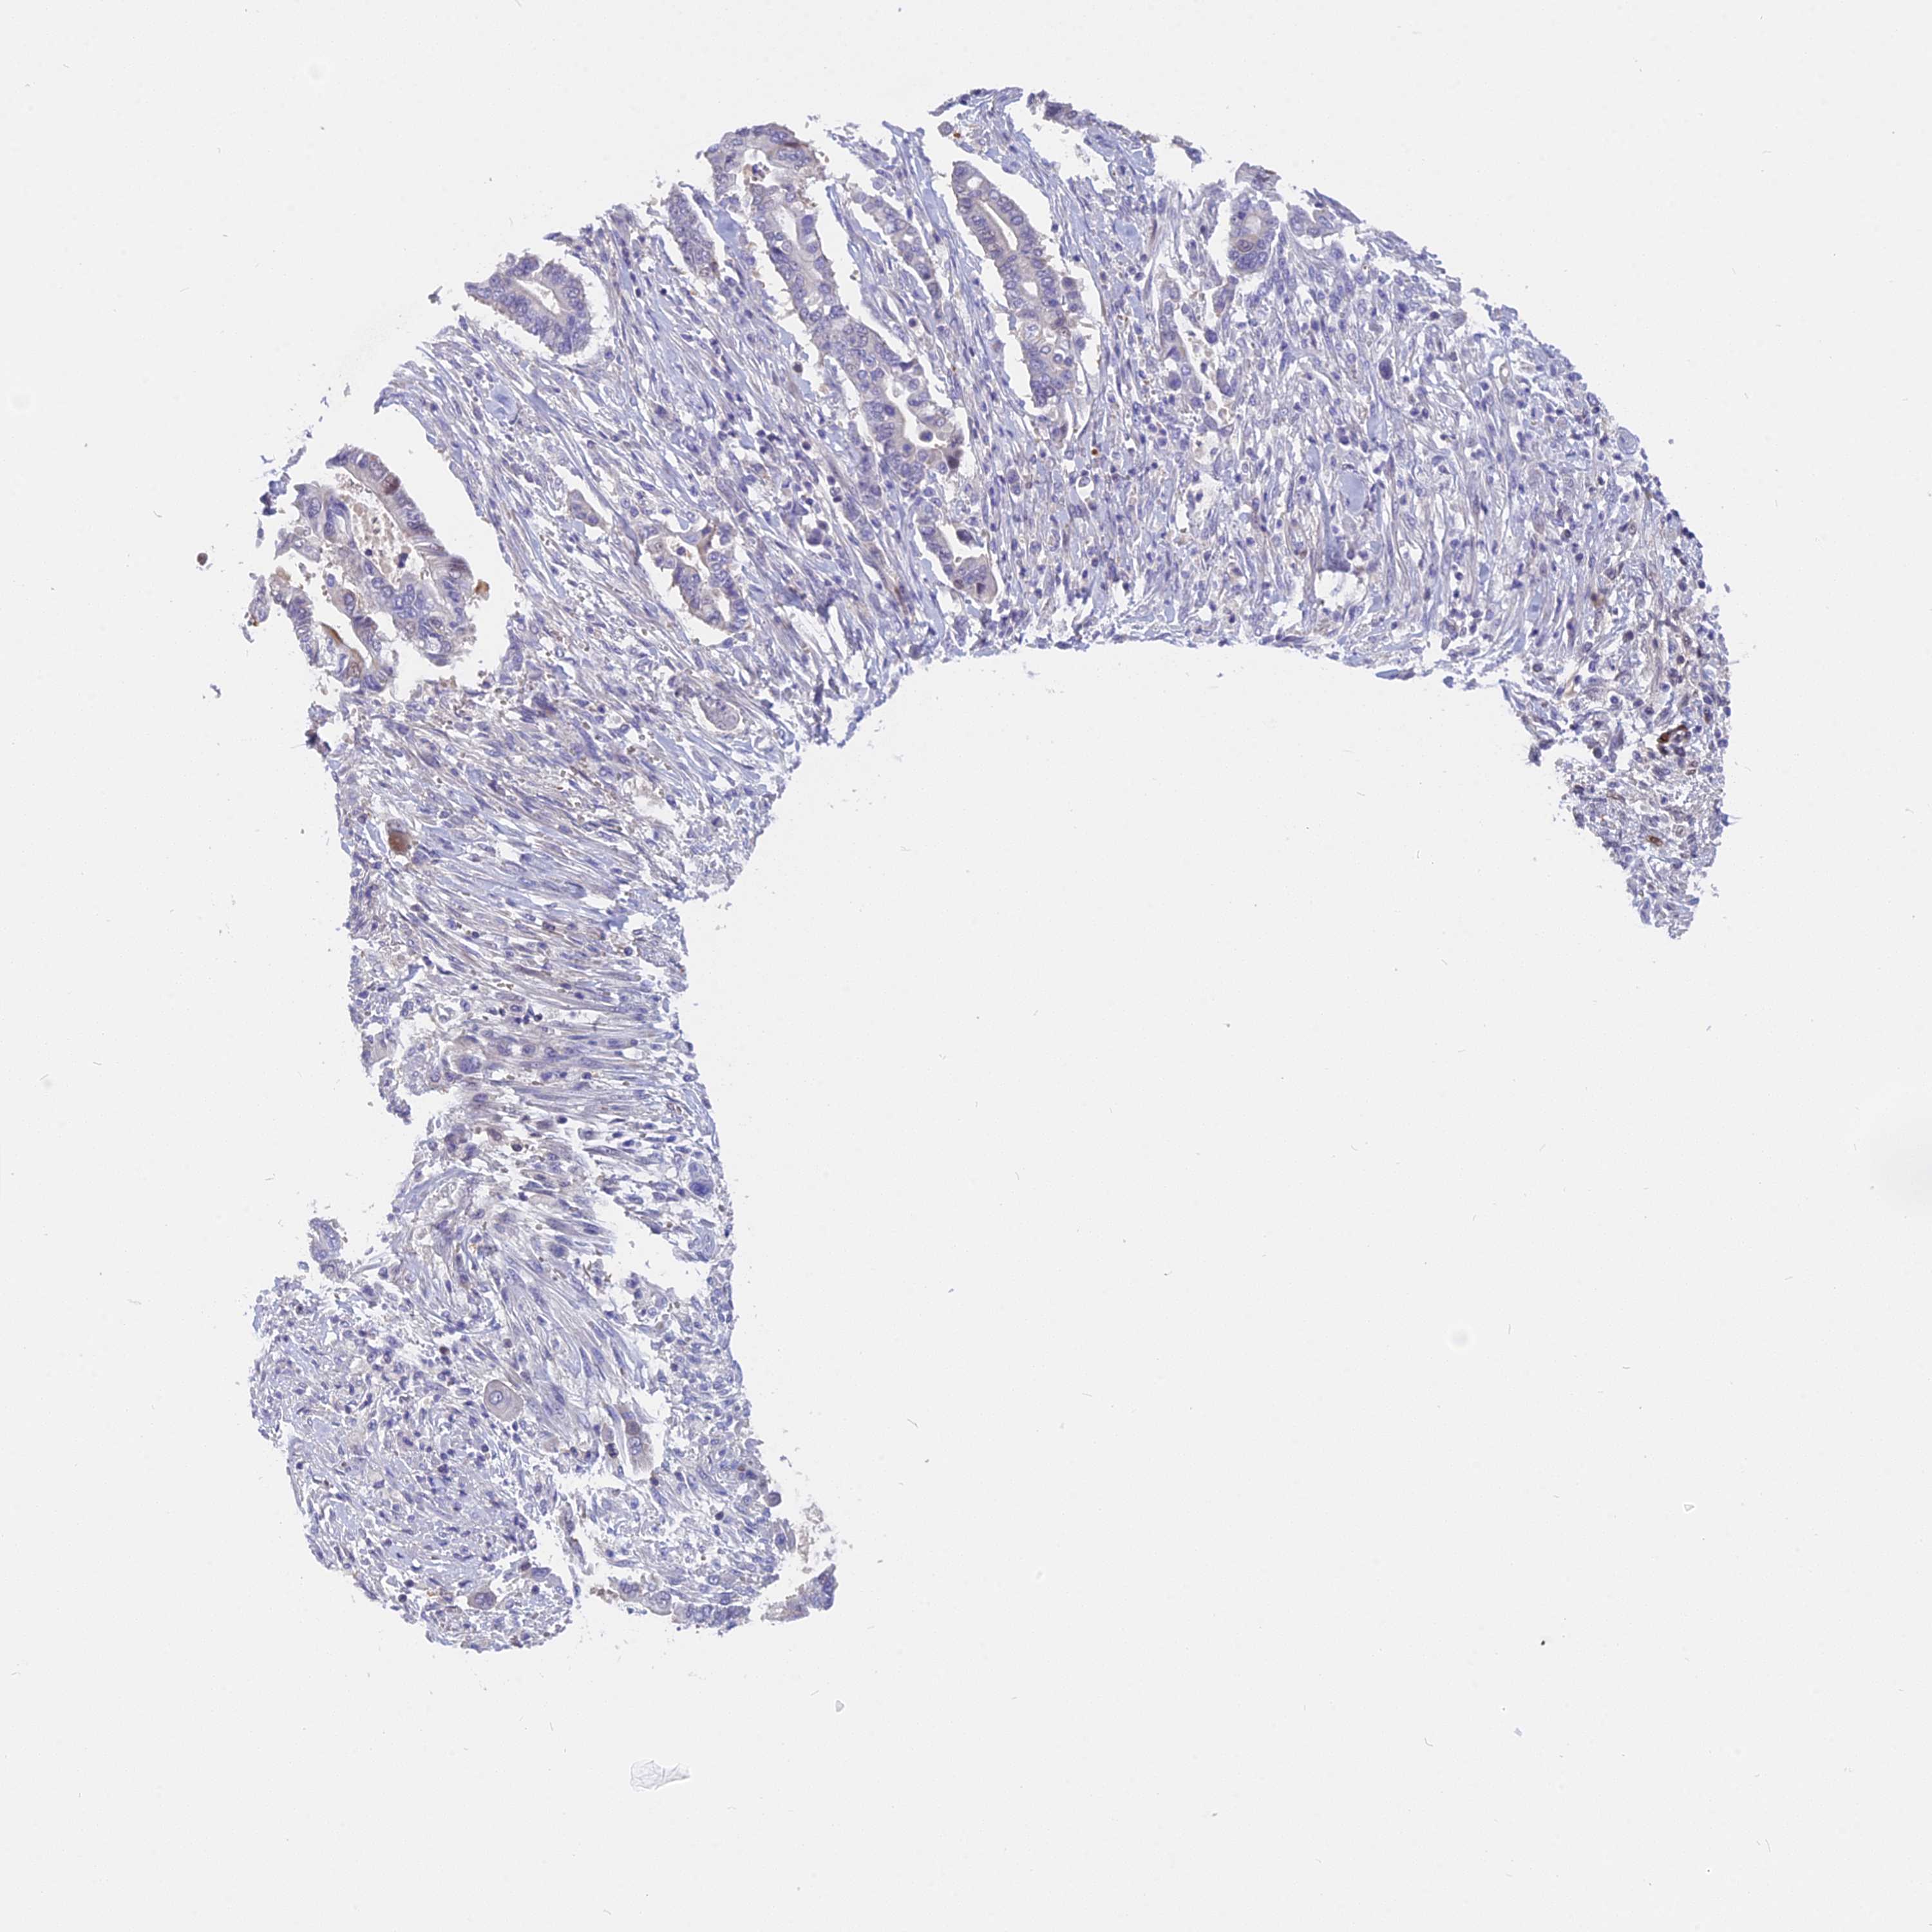

PANCREATIC CANCER - Protein expressioni

A mouse-over function shows sample information and annotation data. Click on an image to view it in a full screen mode. Samples can be filtered based on level of antibody staining by selecting one or several of the following categories: high, medium, low and not detected. The assay and annotation is described here.

Note that samples used for immunohistochemistry by the Human Protein Atlas do not correspond to samples in the TCGA dataset.

Antibody stainingi

Antibody staining in the annotated cell types in the current human tissue is reported as not detected, low, medium, or high, based on conventional immunohistochemistry profiling in selected tissues. This score is based on the combination of the staining intensity and fraction of stained cells.

Each image is clickable and will lead to virtual microscopy that enables deeper exploration of all samples and also displays staining intensity scores, fraction scores and subcellular localization as well as patient and tissue information for each sample.

Antibody HPA043339

Staining

High

Medium

Low

Not detected

Intensity

Strong

Moderate

Weak

Negative

Quantity

>75%

75%-25%

<25%

None

Location

Nuclear

Cytoplasmic/membranous

Cytoplasmic/membranous,nuclear

Adenocarcinoma, NOS